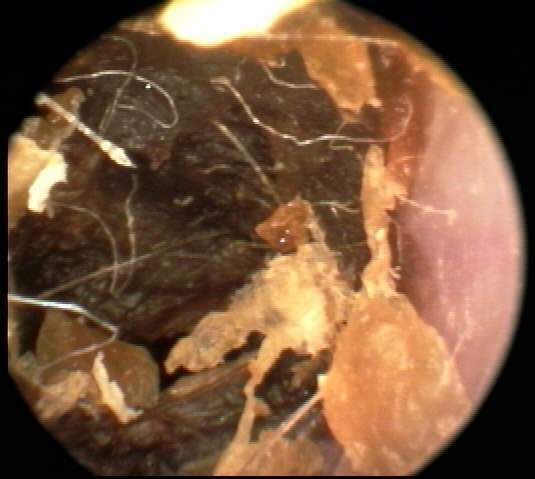

+3: Occlusive major amount present; likely to interfere with insert and circumaural hearing testing, may add a conductive overlay; obstruct hearing aid receiver and vent, reducing effective gain and output. Tympanic membrane not visualized. Removal essential. EXAMPLES:+3/A(25k) | +3/B(27k) | +3/C(27k) | +3/D(17k) | +3/E(19k) | +3F(18k)